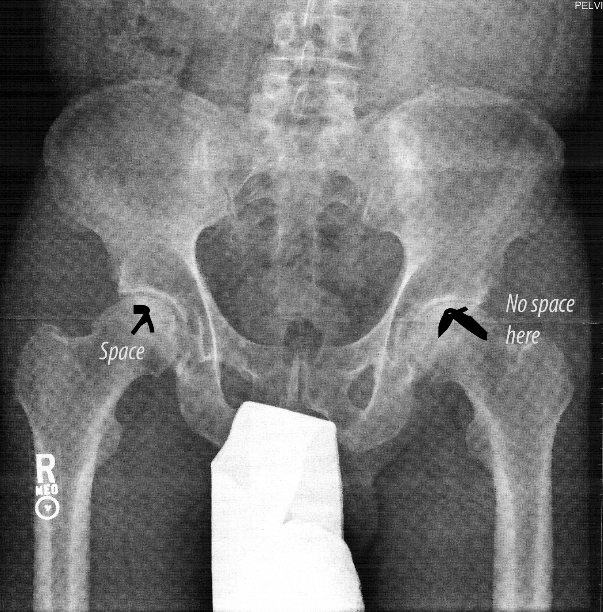

Nine years ago Jadyne noticed that I was walking unevenly. Even Cecile, our next door neighbor, said, “You’re limping.” I saw my GP who recommended exercises that I followed for months. No improvement Finally, I went in for an x-ray.

An X-ray of my hip. No space means new hip. A pair of before and after photos. My current hip is pictured on the right.

This was just a beginning, what my friend and neighbor Chris Anderson called, “a new normal,” a fluid description that was to be applied over and over again.